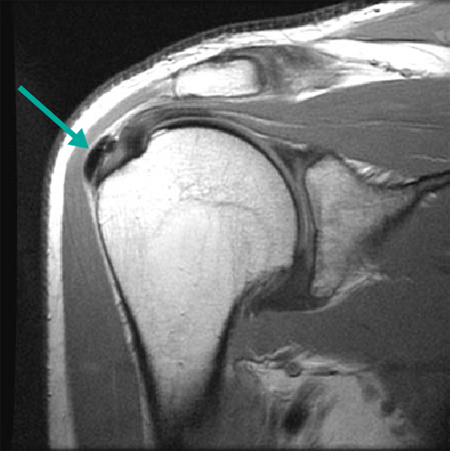

[Figure caption and citation for the preceding image starts]: MRI demonstrating calcific tendinopathy involving the distal central supraspinatusFrom the personal collection of James Wang, PhD [Citation ends].